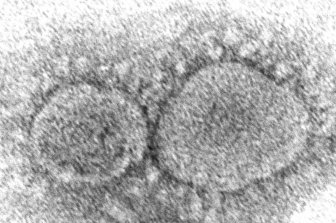

‘Unpredictable pathogen’: New coronavirus study highlights severity of illnessPneumonia, respiratory problems, kidney failure and sepsis among the most common complications found in a large U.S. study of COVID-19 patients.HealthDec 8, 2020

Almost 1M have died from coronavirus. Their deaths taught researchers about treatmentPatients are already benefiting. Though more deaths are expected this fall because of the recent surge in coronavirus infections in the U.S. and elsewhere, there also are signs that death rates are declining and that people who get the virus now are faring better than did those in the early months of the pandemic.HealthSep 27, 2020

Researchers hope manufactured antibodies could help treat COVID-19Manufactured antibodies, which are used to treat some forms of cancer, could also be used for COVID-19, researchers say.HealthAug 4, 2020

Remdesivir has emerged as a possible COVID-19 treatment — what happens next?At present, COVID-19 is a disease with no approved treatments or vaccines.CanadaMay 1, 2020